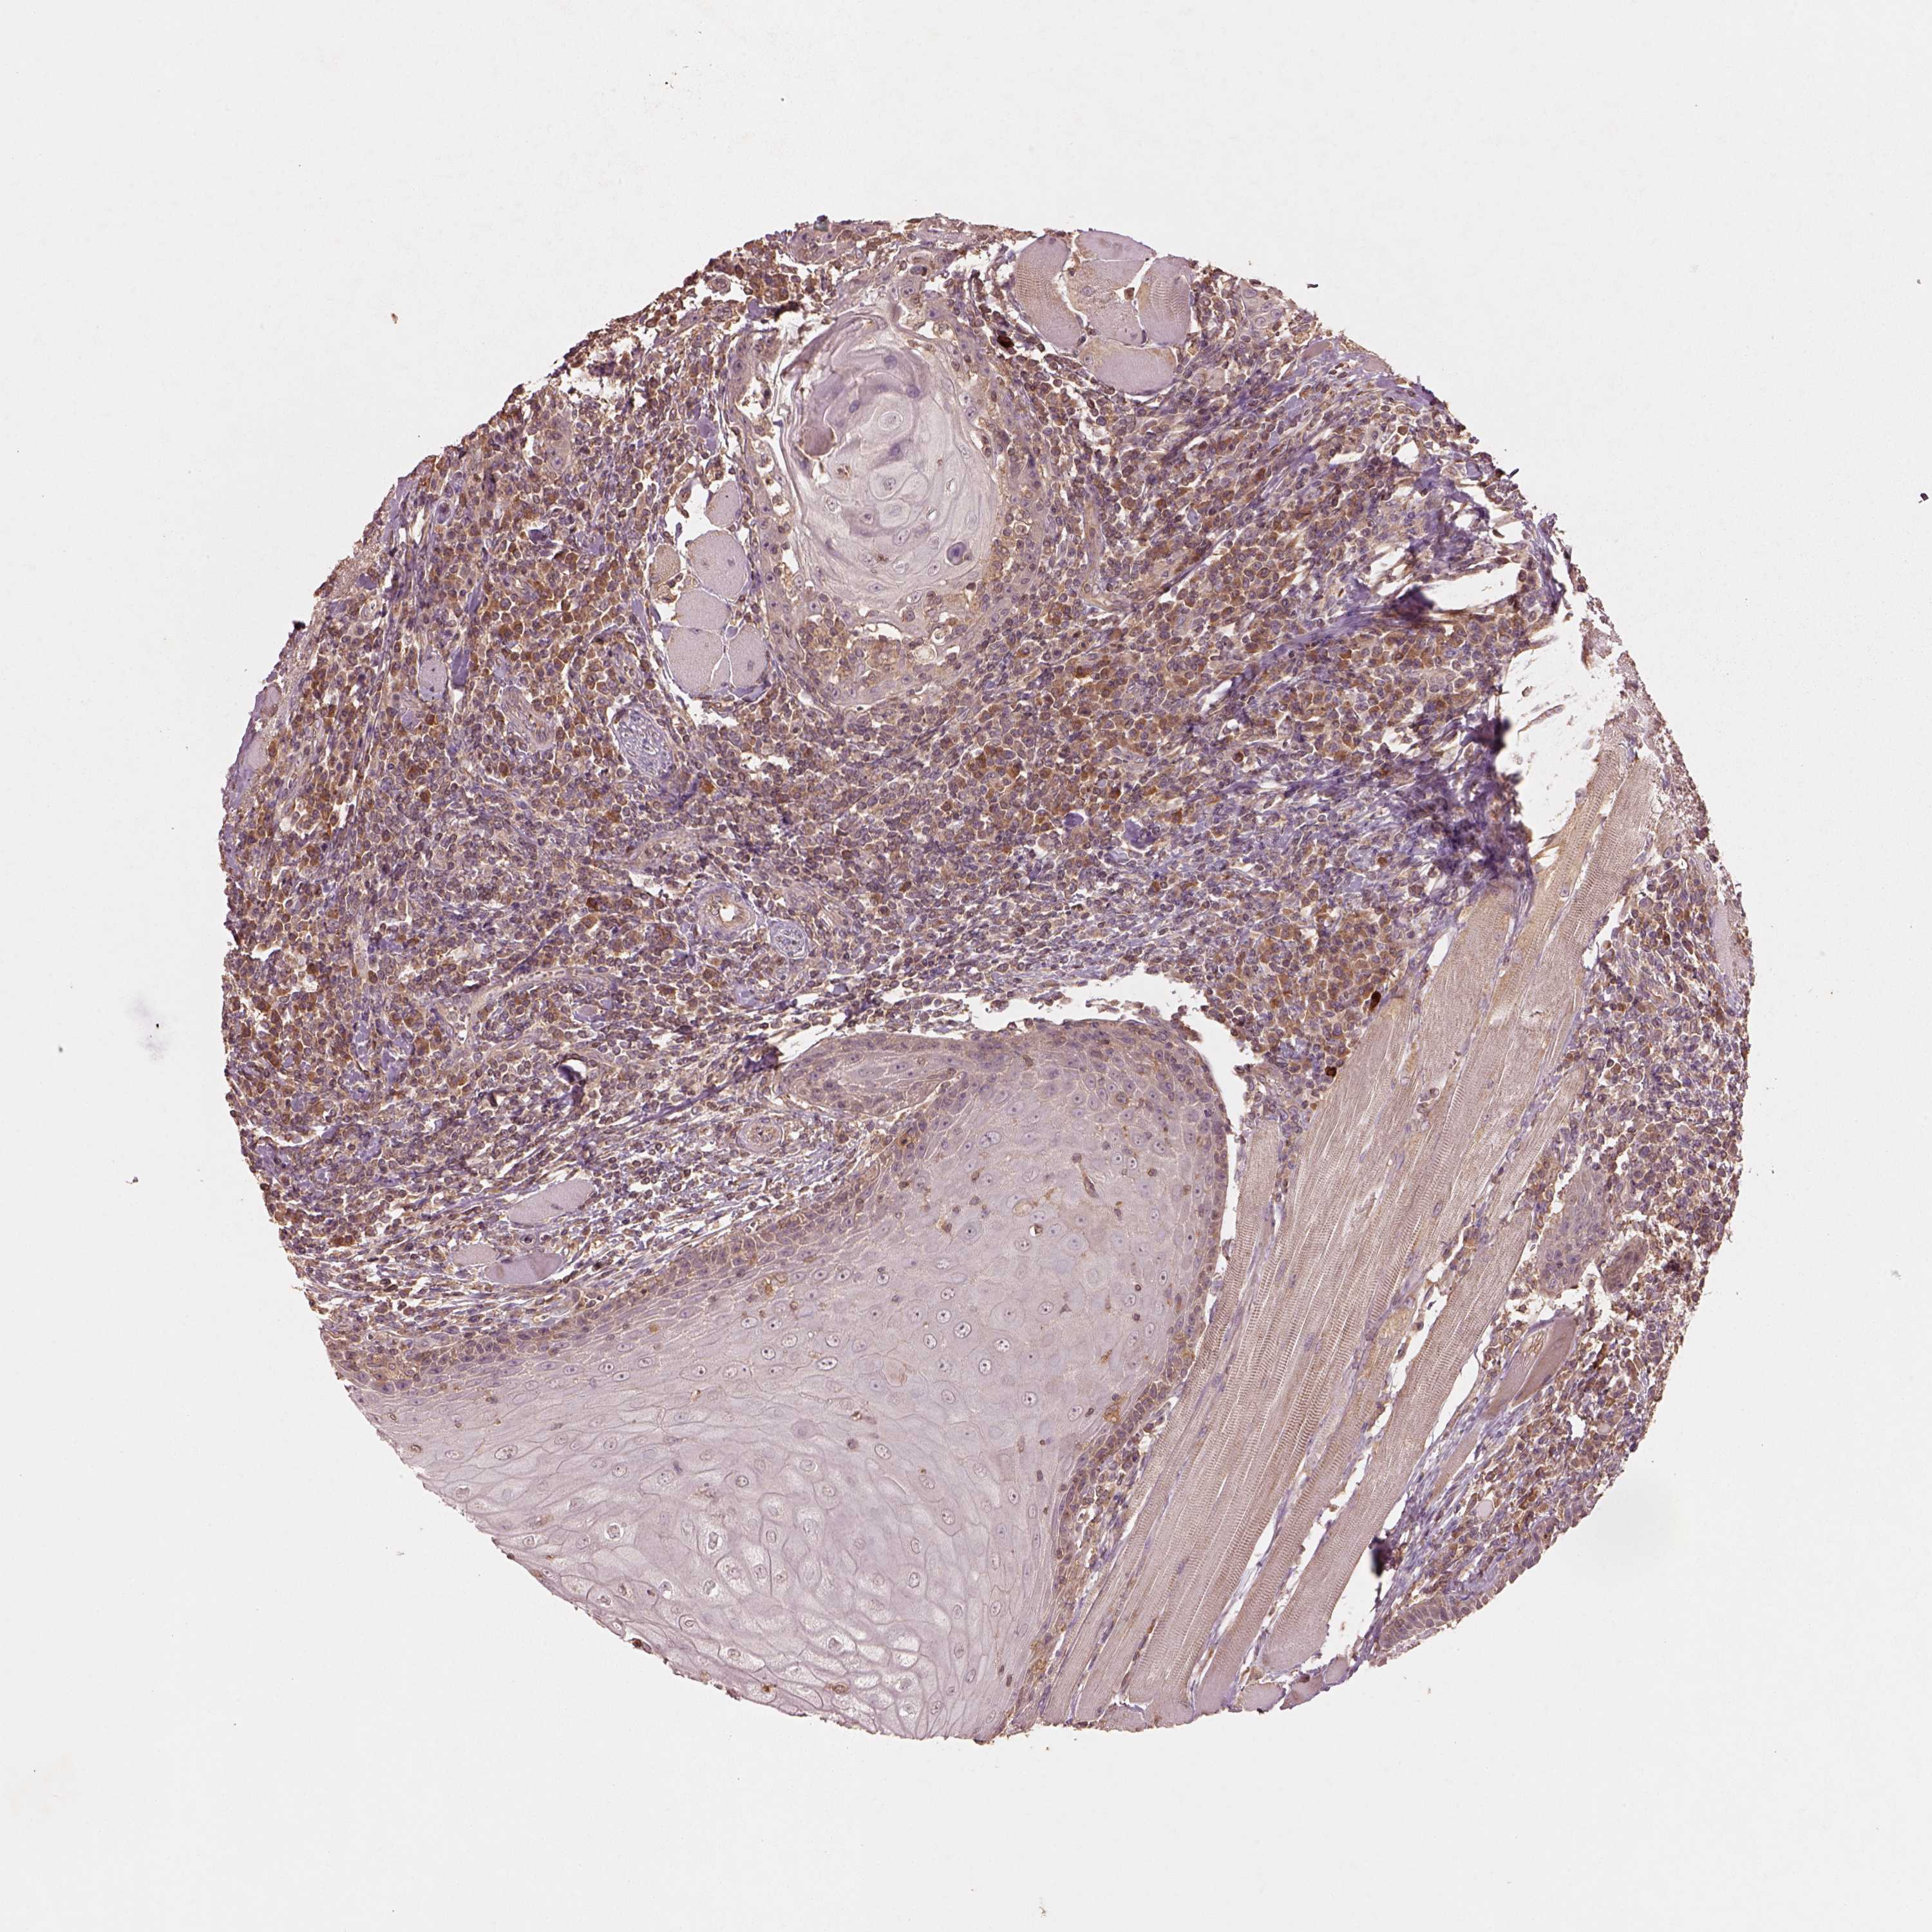

HEAD AND NECK CANCER - Protein expressioni

A mouse-over function shows sample information and annotation data. Click on an image to view it in a full screen mode. Samples can be filtered based on level of antibody staining by selecting one or several of the following categories: high, medium, low and not detected. The assay and annotation is described here.

Antibody stainingi

Antibody staining in the annotated cell types in the current human tissue is reported as not detected, low, medium, or high, based on conventional immunohistochemistry profiling in selected tissues. This score is based on the combination of the staining intensity and fraction of stained cells.

Each image is clickable and will lead to virtual microscopy that enables deeper exploration of all samples and also displays staining intensity scores, fraction scores and subcellular localization as well as patient and tissue information for each sample.

Antibody HPA071341

Antibody CAB004602

Staining

High

Medium

Low

Not detected

Intensity

Strong

Moderate

Weak

Negative

Quantity

>75%

75%-25%

<25%

None

Location

Nuclear

Cytoplasmic/membranous

Cytoplasmic/membranous,nuclear

Squamous cell carcinoma, NOS

Adenocarcinoma, NOS

Neoplasm, malignant, NOS